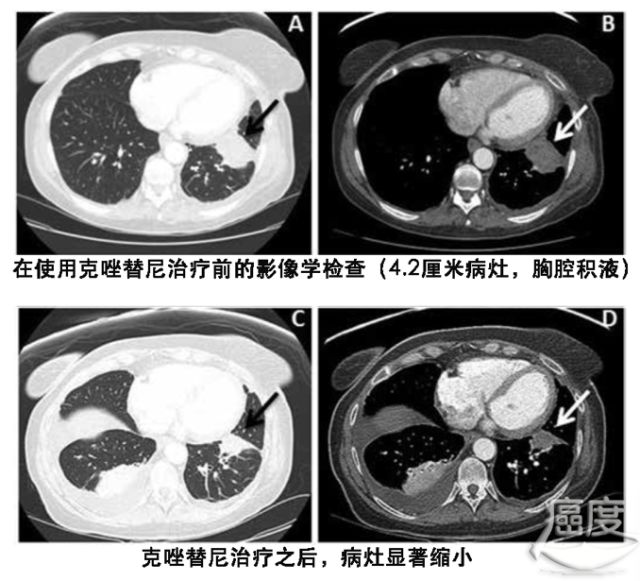

一名55岁的不吸烟的女性在坐飞机之后出现下肢肿胀kras基因突变,胸部计算机断层扫描CT发现不是肺动脉栓塞,在肺部左下叶发现有4.2厘米的肿块,这个肿块导致左肺少量胸腔积液。

基于该患者的分子检测结果,患者开始使用克唑替尼治疗,服药2个月后,肿瘤病灶显著缩小,临床病理评估为部分缓解。肿瘤病灶继续缩小了3个月之后,后面则是9个月的病情稳定期。后面因为克唑替尼出现耐药而中断治疗。